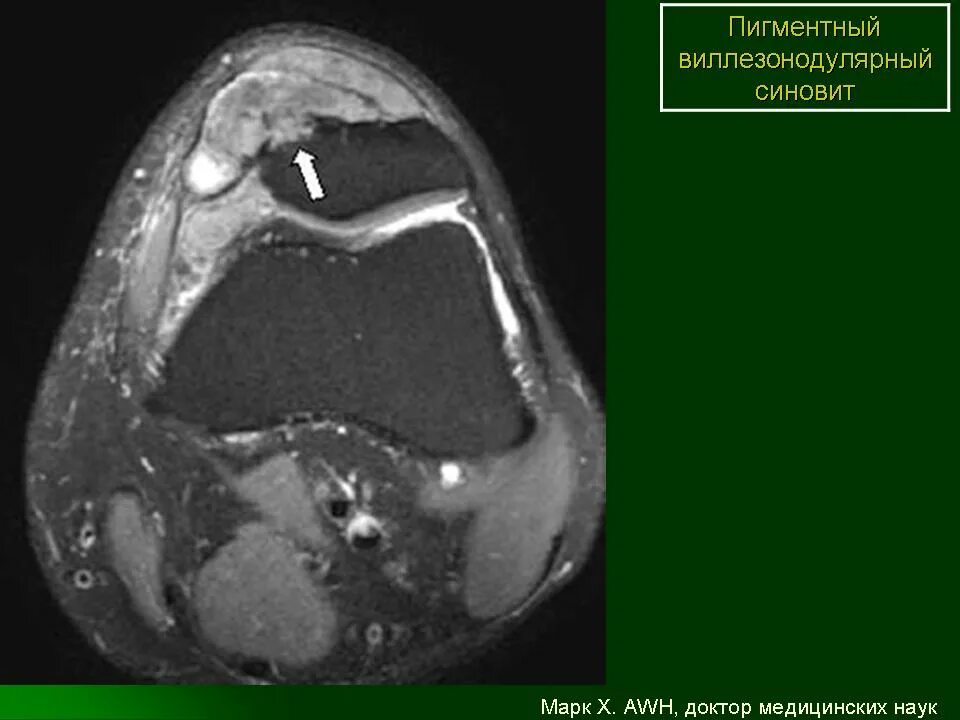

Пигментный виллонодулярный синовит